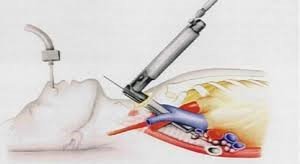

Kəskin mediastinit şübhəsi olan xəstə təcili xəstəxanaya yatırılır, diaqnoz qoyulan kimi aktiv dəstək, antibiotikoterapiya başlanılır və cərrahi müalicə həyata keçirilir. Kəskin mediastinitin müalicəsində cərrahi müalicə əsas tədbirdir və iki məqsədlə yerinə yetirilir: irinliyin sanasiyası-drenajı və səbəbin aradan qaldırılması (Şəkil 12).

Şəkil 12. Divararalığının drenajı

Sanasiya-drenaj üçün divararalığına yuxarıdan, transsternal, transtorakal yollarla müdaxilə etmək olar. Səbəbi aradan qaldırmaq üçün edilən əməliyyatlar səbəbdən asılı olaraq dəyişir.